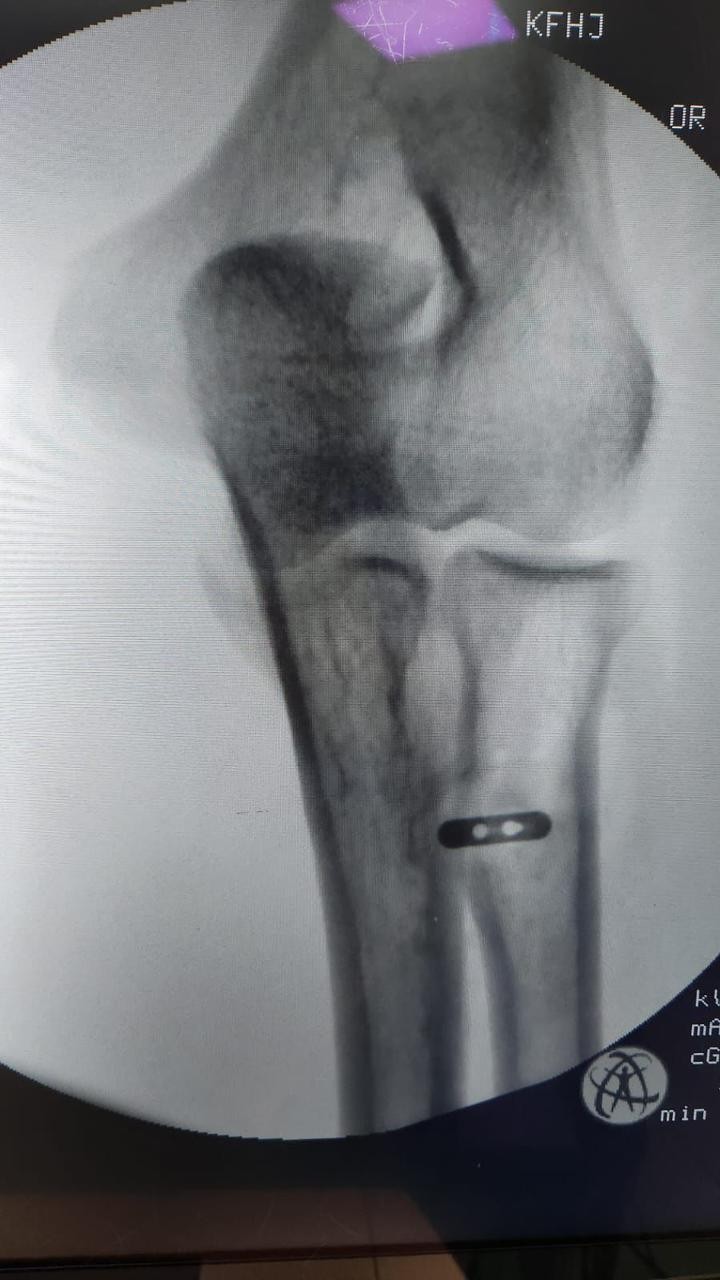

تمكن فريق طبي في جراحة العظام بمستشفى الملك فهد بجدة من إجراء عملية لمريض في الأربعين من عمره ، و إعادة وتره المقطوع ، نتيجة لتعرضه قبل شهر لقطع في العضلة التي تسمى البايسيبس ، و قد تمكن الفريق من إعادة و تثبيت الوتر المقطوع لمكانه بقيادة الدكتور شهاب بوسطجي استشاري الزمالة الألمانية في جراحة العظام و إصابة الملاعب بمستشفى الملك فهد بجدة .

و أشار الدكتور بوسطجي رئيس الفريق الطبي الذي أجرى العملية أنه قد تم إجراء الفحوصات اللازمة للمريض قبل العملية من أشعة رنين مغناطيسي ، مضيفاً إلى أن هذا النوع من العمليات يُعد نادراً و من العمليات الدقيقة جداً التي تحتاج وقتاً للعودة لوضعها الطبيعي .